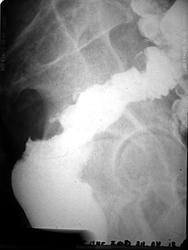

Пациент с жалобами на запоры. Ирригоскопия после RRS (тубус после 10 см не прошел).

Коллега, а обзорный снимок не делали и что написали по status loclis на RRS? Какое-то органическое поражение дистальных отделов толстой кишки с массивной циркулярной инфильтрацией и боковыми затёками  контраста ( рак ? болезнь Крона? неспецифический язвенный колит?)

Извините за молчание (уезжал). На RRS - циркулярная бугристая опухоль грязно-серого цвета. На гистологии - аденокарцинома. Насчет обзорного снимка - зачем? - выложены прицельные РГ.